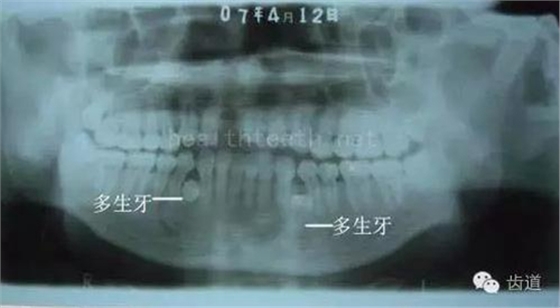

因?yàn)楸旧聿桓阏衬げ。占降牟±邢?,大多是同事收?/span> 頰粘膜扁平苔蘚 舌粘膜扁平苔蘚 舌緣創(chuàng)傷性潰瘍 長期戴活動義齒不當(dāng)或是戴不良修復(fù)義齒造成的口腔粘膜潰瘍,應(yīng)該引起高度警惕,因?yàn)檫@種潰瘍?nèi)菀装┳?/span> 黑毛舌 舌息肉,該患者同時伴有胃、食管息肉,后來看內(nèi)科了,具體情況不詳 四、孩子的牙齒問題 乳牙未退,牙根穿出牙齦對上唇粘膜造成刺激 乳牙滯留,也是孩子在退牙過程中最容易遇到的問題 五、牙齒發(fā)育上的問題 變色牙 氟斑牙 釉質(zhì)發(fā)育不全 四環(huán)素牙 牙神經(jīng)治療后的牙齒變色 10歲孩子剛剛萌出的牙齒變色 2、埋伏牙 左上乳3滯留,恒3未見萌出,曲面斷層片顯示牙齒埋伏 通過CT片確定埋伏牙齒具體的位置,顯示距離左側(cè)上頜竇很近,偏唇側(cè),這為手術(shù)定位提供了方便 手術(shù)中切斷、完整拔出,未損傷上頜竇 其他埋伏牙 3、多生牙 病例1 病例2 病例3,同時多生兩顆牙齒 4、各種畸形牙 畸形過小牙 融合牙:恒牙和乳牙都可以發(fā)生融合的情況(兩顆牙齒長在了一起) 畸形中央尖:在牙齒的中央,兩個牙尖之間又多長出一個牙尖,由于進(jìn)食的磨耗很容易造成磨穿,神經(jīng)就會與外界相通,出現(xiàn)牙髓炎的癥狀 六、牙齒的外傷 牙冠折斷 牙根折斷 烤瓷牙打樁修復(fù)后牙根折斷 外傷后牙齒的全脫位,應(yīng)該保留牙齒盡早做再植手術(shù) 七、牙齒的慢性損傷 牙頸部楔狀缺損 牙冠劈裂及完整拔除后的情況 牙根縱裂及拔除后的情況 牙隱裂,牙齒表面有肉眼看不到的裂紋,細(xì)菌通過其進(jìn)入牙髓,容易出現(xiàn)牙髓炎癥狀,嚴(yán)重可以造成牙齒的劈裂 這是一位來中國學(xué)習(xí)的俄羅斯大學(xué)生的牙齒,已經(jīng)做過了根管治療,牙齒咬合面有隱裂,通過鋼絲結(jié)扎固定,做鑄造金屬冠修復(fù)。 八、牙髓炎、根尖周炎 下面圖片都是慢性根尖周炎的病例,有了齲齒,進(jìn)一步發(fā)展就是牙髓炎,如果此時沒有得到及時的治療,疾病會逐漸發(fā)展破壞到根尖的骨質(zhì),將骨質(zhì)破壞后就在牙齦上出現(xiàn)一個膿瘺,此時患者不再感覺到牙齒的疼痛了,往往忽視了治療,但是這種不痛并不是疾病好轉(zhuǎn)了,而是因?yàn)榧膊〉难仔詽B出得到了引流,這個膿瘺會出現(xiàn)有時候變大了,有時候又變小了,但是如果不治療是不會自己愈合的,只有經(jīng)過完善的根管治療后才有好轉(zhuǎn)的可能,但是在疾病的治療中時間是起決定作用的,時間拖得越晚,好轉(zhuǎn)的可能性越小,經(jīng)過根管治療后如果膿瘺還是沒有消失,就需要做根尖刮治術(shù),如果仍然沒有好轉(zhuǎn),就只能做根尖切除術(shù)了,這對牙齒的穩(wěn)固是不利的。下面圖片中在膿瘺中插入了一個牙膠尖,是我們做根管充填用的材料,是非常軟的,就是在口腔牙齦瘺管的地方插進(jìn)去,通過拍牙片可以清晰地看到它到達(dá)的位置,從而確定發(fā)病的牙齒,此處是為了讓大家看得更清楚。 門牙兩個膿瘺 烤瓷牙修復(fù)后牙齦出現(xiàn)兩個膿瘺,插入牙膠尖,牙片顯示牙膠尖到達(dá)的位置就是根尖炎癥的位置,根尖骨質(zhì)密度降低(發(fā)黑的地方) 牙齒根尖膿瘺,治療前、中、后的圖片對照,完善根管治療后膿瘺明顯消失了 牙髓炎和根尖炎治療的關(guān)鍵就是根管治療 合格的根管充填治療 不良的根管充填治療 九、關(guān)于智齒(第八顆牙) 四顆長不出來的智齒 智齒反復(fù)發(fā)炎造成的頰瘺,膿腫切開引流后面部會留疤 智齒造成的頜骨囊腫,手術(shù)切除后需要植骨 十、各種錯合畸形 開合 深覆合 深覆蓋,上頜前突 反合(地包天) 牙齒排列擁擠 來源:牙醫(yī)愛看的 KQ88口腔醫(yī)學(xué)網(wǎng)